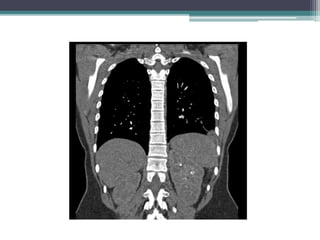

Avaliação diagnóstica

• Exames de imageamento

▫ Radiografia de tórax;

▫ Tomografia computadorizada;

▫ Imageamento por ressonância magnética;